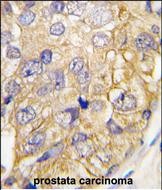

- Formalin-fixed and paraffin-embedded human prostata carcinoma tissue reacted with DRAGON (RGMB) (C-term) (Cat.#P30230), which was peroxidase-conjugated to the secondary antibody, followed by DAB staining. This data demonstrates the use of this antibody for immunohistochemistry; clinical relevance has not been evaluated.